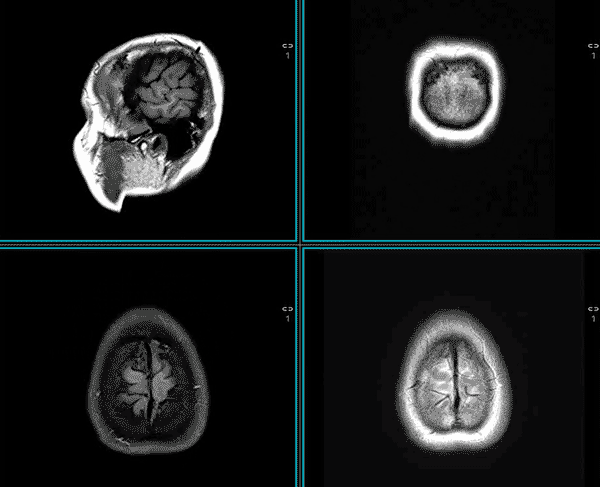

رادیولوژی شاخهای از علم پزشکی است که با استفاده از فناوریهای تصویربرداری، به مشاهده ساختارهای داخلی بدن کمک میکند. برخلاف معاینههای بالینی که به بررسی علائم بیرونی بیماری میپردازند، رادیولوژی پزشک را قادر میسازد درون بدن را بهصورت دقیق و غیرتهاجمی بررسی کند.

اهمیت تخصص در تفسیر تصاویر

تجهیزات پیشرفته بهتنهایی کافی نیستند. تجربه و دانش متخصص رادیولوژی برای تفسیر صحیح تصاویر و ارائه گزارش دقیق بسیار کلیدی است. حتی کوچکترین جزئیات در یک تصویر میتواند مسیر درمان بیمار را تغییر دهد.

در مرکز تصویربرداری ولیعصر، ما از فناوریهای تصویربرداری دیجیتال بهره میبریم که باعث کاهش میزان اشعه، افزایش کیفیت تصویر و تسریع فرآیند تشخیص میشود. همچنین، تمام تصاویر به صورت دیجیتال ذخیره و در دسترس پزشکان معالج قرار میگیرد.